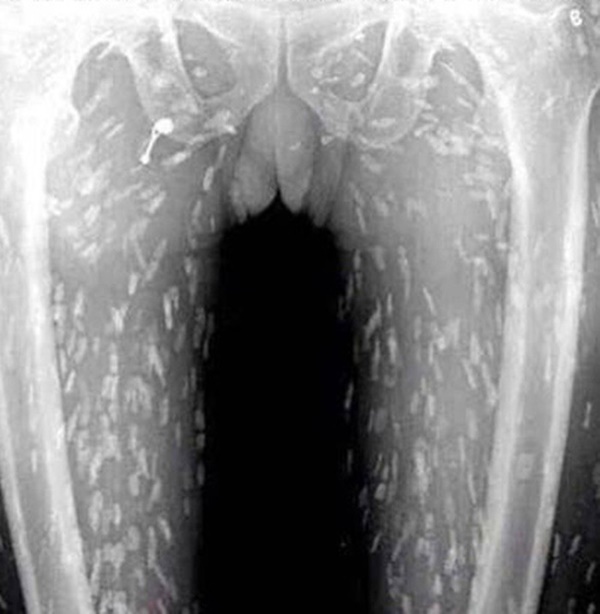

Vào tháng 3 năm ngoái, các bác sĩ tại Bệnh viện Trường Đại học Y Quý Châu đã vô cùng bất ngờ khi phát hiện 30 quả trứng sán dây "nở" bên trong não một người đàn ông trung niên họ Wu nhập viện do đau đầu và buồn nôn trong suốt nửa năm. Họ tin rằng sán dây lợn đã xâm nhập vào não ông ta bởi ông đã ăn thịt lợn nhiễm sán hoặc chưa chín.

Số trứng sán mà bác sĩ lấy ra từ bên trong não của ông Wu.

Ông Wu kể với các bác sĩ rằng bản thân ông từng ăn thịt sống, sau đó ông thấy xuất hiện các triệu chứng đau đầu, nôn mửa và co giật. Chụp cộng hưởng từ (MRI) não ông Wu cho kết quả có hàng chục trứng sán dây, chúng đã khiến ông này bị não úng thủy. Đội ngũ bác sĩ tại bệnh viện đã tiến hành phẫu thuật mở sọ cho ông Wu và loại bỏ số trứng cùng sán dây khỏi não của bệnh nhân 46 tuổi này.

Bác sĩ phải tiến hành phẫu thuật mở sọ cho ông Wu và loại bỏ số trứng cùng sán dây.

Những con ấu trùng vẫn còn động đậy bên trong quả trứng, vì vậy, khi phẫu thuật các bác sĩ đã vô cùng cẩn trọng để không khiến trứng vỡ. Sau cuộc phẫu thuật, ông Wu còn trải qua nhiều cuộc điều trị khác để loại bỏ hoàn toàn sán dây bởi nếu vẫn còn sót lại, chúng có thể gây tổn thương mô não của ông.